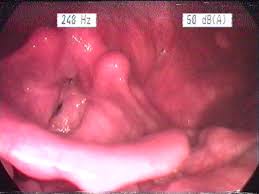

2️⃣ Arka burun kanaması (posterior epistaksis)

-

Daha nadir ama daha tehlikelidir

Kan çoğunlukla boğaza doğru akar

Yaşlılarda ve hipertansiyon hastalarında sık

Nedeni:

Burunun arka ve derin damarları (kalın, yüksek basınçlı)

Risk:

⚠️ Yüksek

⚠️ Aspirasyon, ciddi kan kaybı, hastaneye yatış gerekebilir